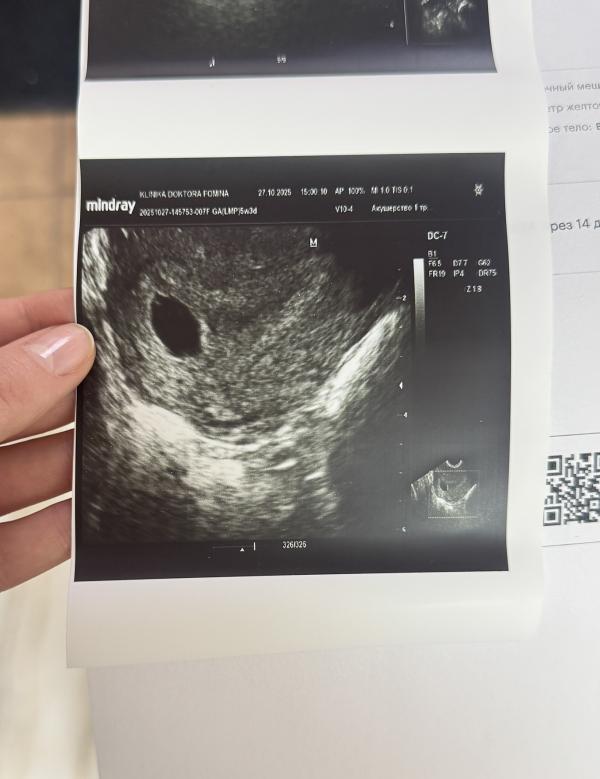

Сегодня была на узи 🥹

Все отлично, прикрепилось там где надо ♥️